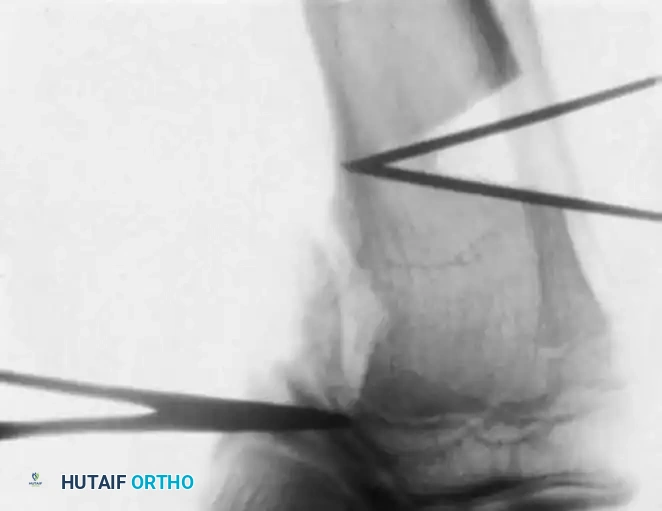

- Osteotomy Execution: Guide pins are placed under fluoroscopic guidance to define the osteotomy plane. The cut is made distal to the tibial tubercle to ensure the extensor mechanism remains attached to the proximal fragment.

- Deformity Correction: The distal fragment is translated laterally, angulated into valgus, and externally rotated to correct the multiplanar deformity.

- Fixation: Fixation depends on surgeon preference and patient age. Options include crossed Kirschner wires incorporated into a long-leg cast, rigid internal fixation (plates and screws), or external fixation (Ilizarov or Taylor Spatial Frame), which allows for gradual postoperative correction.